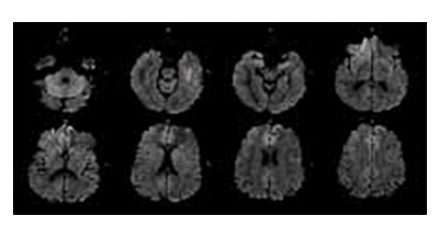

• 확산 강조 영상(Diffusion Weighted Imaging)

확산 강조 영상

(Diffusion Weighted Imaging)

생체 내에서 분자의 확산 정도 차이를 측정하여 영상화 함으로써 3시간 내에 발생한 조기 뇌 경색(brain stroke) 진단이 가능해진 것은 물론이고 조직의 농양, 조직 괴사, 종양의 감별까지도 가능합니다.